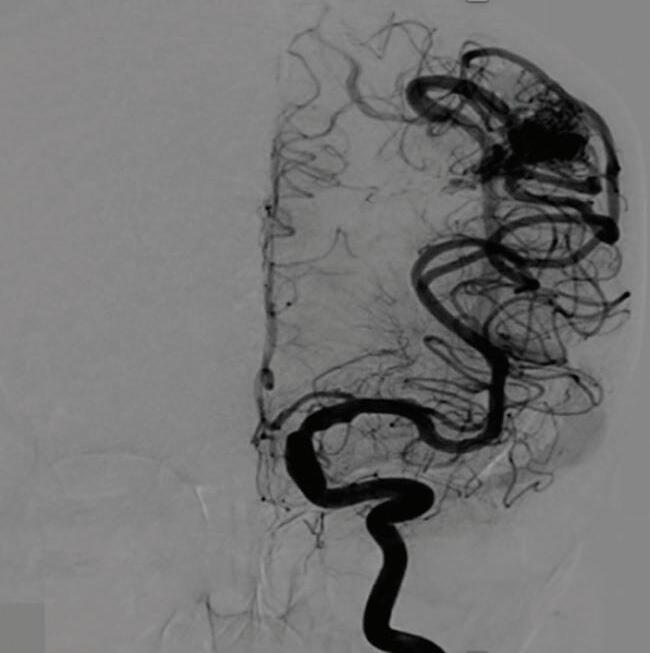

Fig. 1-8. (a-c) RNM T1 com contraste, cortes sagital (a), coronal (b) e axial (c) demonstrando MAV não rota com nidus localizado no lobo occipital à esquerda (setas longas). (d) Arteriografia digital cerebral com injeção de contraste via carótida direita (AP) mostrando a contribuição da carótida direita na irrigação da MAV contralateral. (e,f) Com injeção de contraste via carótida esquerda, em Perfil e AP respectivamente, observa-se nidus compacto nutrido por ramos da artéria cerebral média à esquerda e a veia de drenagem precoce se dirigindo para o seio sagital superior. Projeções em AP (g) e em perfil (h) demonstrando a contribuição do sistema vertebrobasilar por meio de ramos distais da artéria cerebral posterior à esquerda e drenagem para os seios sagital superior e sigmoide à esquerda (setas curtas).